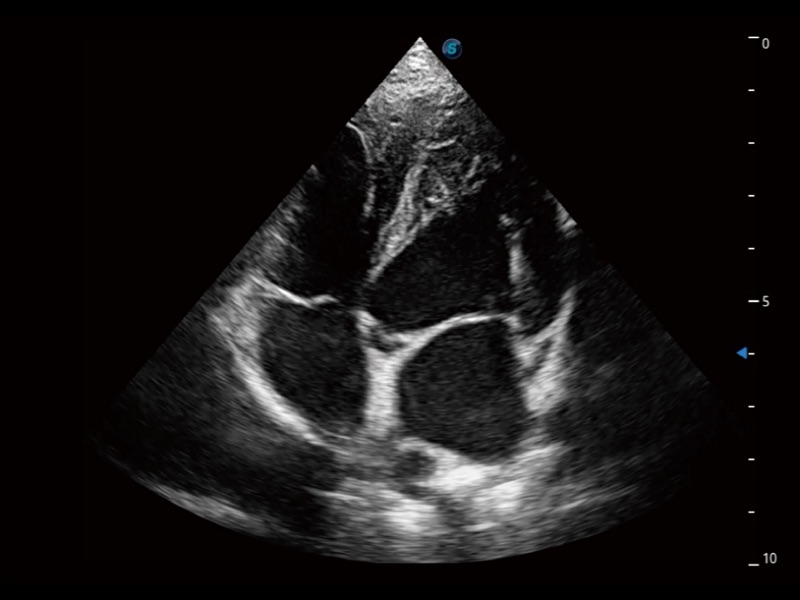

通过360度任意调节3条M型取样线,在同一心动周期上观察心脏不同位置的运动曲线,得到准确的心功能测量数据,有效评估心肌运动及左心室功能。

ProPet 70专为动物医生设计,对不同的动物体型和生理结构作出了针对性的优化。通过动物影像专用软件,可满足个性化的应用需求,帮助动物医生获得更精确的诊断数据。

提供解剖示意图、标准超声图像、扫查手法图和操作者实时检查图像,指导操作者进行标准切面的正确扫查。